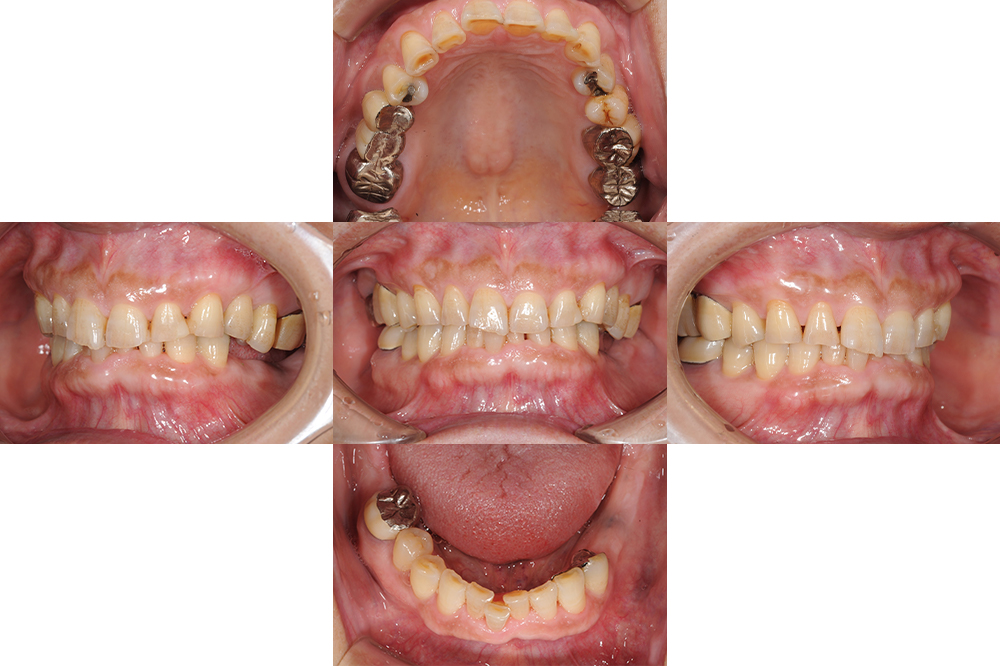

治療内容 ・インプラント

・セラミック修復

治療期間 9ヶ月

治療費用 250万円

元々全体的に歯と歯の間がすいていて食渣が挟まりやすかったが、インプラントを入れることで奥歯にしっかりしたサポートが回復され、歯の隙間が自然と詰まり、物詰まりも軽減することができた。

After